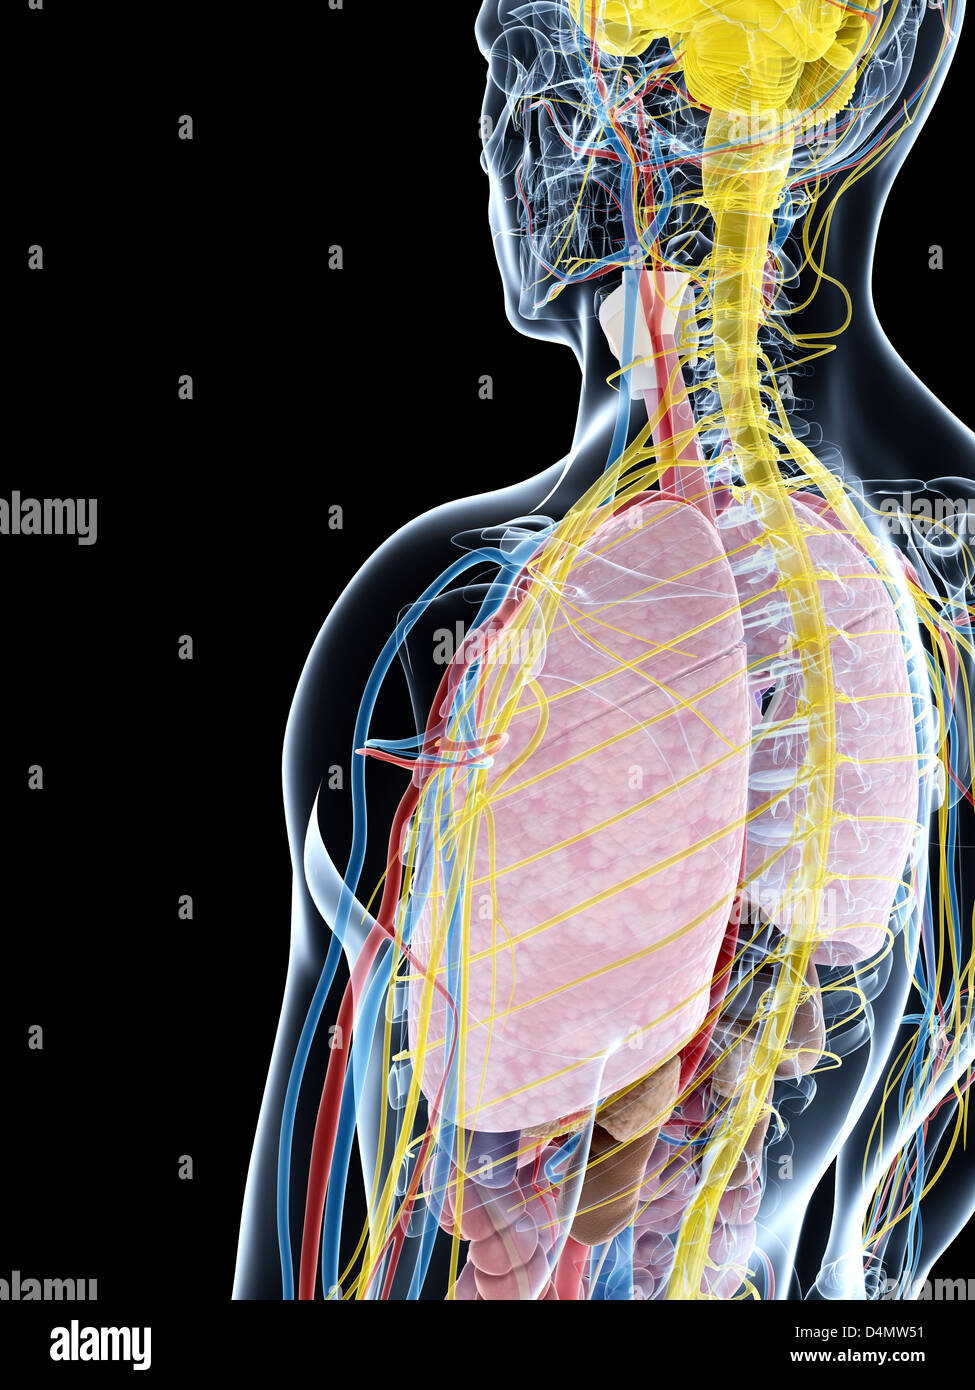

RFDGYRD7–Männliche Anatomie, inneren Organe allein, volle Atmungs- und Verdauungssystem, mit einigen Organen Cutaway. Anatomie-Bild.